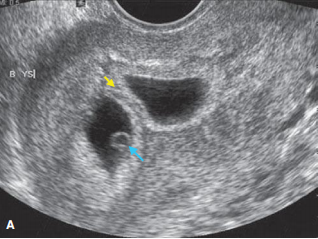

多年来,贵州航天医院各科室紧跟医学前沿,不断强技术、补短板,大力开展新技术、新项目,完成了许多高精尖、高难度、本地区“首例”的技术,填补了医院医疗技术空白,满足了群众日益增长的医疗需求。 复杂性双胎超声监护耗时耗力,技术难度大,风险高,为填补本地区复杂性双胎的超声监护技术空白,我院超声科在遵义市率先开展了此项技术,有效满足了双胎孕妇产检需求,保障了双胎新生儿的平安健康。 本期,我们将为大家带来超声科特色技术——复杂性双胎的超声监护。 案例分享 案例一 28岁的孕妇,自然受孕,怀有单绒毛膜双羊膜囊双胎(MCDA),在我院定期产检的过程中,孕32周超声检查发现两个胎儿的大脑中动脉血流流速(MCA-PSV)相差>0.7倍数的正常值(MoM),高度怀疑发生了双胎贫血红细胞增多序列征(TAPS)。为进一步明确诊断,产科立即组织超声科、手术室、新生儿科等科室进行多学科会诊(MDT),诊断为:双胎贫血红细胞增多序列征(TAPS),在征得孕妇及其家属的同意后,决定提前分娩,及时保障了两名胎儿的生命和健康。 双胎大脑中动脉血流 双胎贫血红细胞增多序列征(TAPS) 案例二 一名26岁的孕妇,是完全双角子宫,且为左侧子宫妊娠,怀有单绒毛膜双羊膜囊双胎(MCDA),一直在我院规律产检,孕16周时,超声检查发现双胎生长不一致,体重相差超过25%,考虑子宫畸形合并早发选择性胎儿宫内生长受限。孕妇在咨询相关上级医院专家后,得到减胎的建议,又前来我院咨询,在我院超声科和产科的合作下,查阅了大量文献、认真评估检查报告后,建议孕妇继续双胎妊娠。在规律、严密的超声监护下,双胎除体重差异外未出现严重胎儿并发症,在34周进行了分娩,截至目前,新生儿生长发育均正常。 胎儿生长曲线及子宫畸形三维重建 出生时体重差异 十月龄时 案例三 一名30岁的孕妇,自然受孕,怀有单绒毛膜双羊膜囊双胎(MCDA),在孕22周时超声检查发现双胎发生了选择性胎儿宫内生长受限,遂转诊到上级医院拟行胎儿镜治疗,但在行治疗的前一天,较小的胎儿在宫内发生死亡,在充分与孕妇及家属沟通后,要求继续妊娠,在定期规范的产检下,严密监测胎儿生长发育及胎儿颅脑MRI影像,最终在孕37周时通过剖宫产分娩,目前新生儿生长发育情况良好。 双胎之一胎死宫内(右图) 贵州航天医院自2021年开展复杂性双胎的超声监护以来,已服务大量双胎孕妇,集齐了所有单绒毛膜双羊膜囊双胎(MCDA)并发症病例,由经验丰富的超声医师进行此项检查,产科专业团队进行双胎的规范化监护和分娩,并与重庆医科大学附属第一医院建立了转诊通道,能够及时获得该院专家的指导和支持,为广大孕产妇提供优质、全面的医疗保障。 点击跳转贵州航天医院便民服务电话 什么是复杂性双胎的超声监护 “双胎”被称为产科之王,单绒毛膜双胎则为王中王,主要是因为单绒毛膜双羊膜囊双胎(MCDA)两胎儿共用一个胎盘,胎盘中存在血管吻合。 双胎妊娠的产前筛查及诊断主要依靠超声,相对于单胎妊娠,双胎妊娠并不是单胎检查的重复,双胎妊娠尤其是复杂性双胎的超声诊断更为重要的是关注双胎间循环的关联,双胎间生理及病理改变的相互影响,双胎间血流动力学监测及双胎间差异比较。 超声如何诊断 复杂性双胎并发症 在孕14周以前,超声要明确双胎的绒毛膜性:是单绒毛膜(MC)还是双绒毛膜(DC);孕10周前,可以通过孕囊的个数确定绒毛膜性;孕11周—14周,可以通过胎儿的性别、双胎之间隔膜的厚度、双胎儿分隔膜处胎盘的形态等来区分绒毛膜性。 双绒毛膜双胎的管理和单胎差不多,基本不需要增加超声检查的频次。单绒毛膜的管理相对谨慎,按照国际国内指南规范,单绒毛膜双胎自第16周起,每两周对双胎儿进行生长发育评估及血流检查。 复杂性双胎的超声监护,对超声医生技术要求较高,孕早期需对双胎的绒毛膜性进行精确判断;产科医生根据绒毛膜性制定孕期的产检计划;超声医生掌握胎儿宫内情况,及时与产科医生沟通,精确了解胎儿宫内安危后制定合适的治疗方案,给出适当的终止妊娠时机;复杂性双胎一般都面临早产的风险,所以新生儿团队的专业保障不可或缺,降低新生儿出生后的并发症及提高新生儿生活质量。复杂性双胎的较好妊娠结局,是通过孕期超声科、产科紧密合作,及新生儿出生后新生儿科管理多学科团队合作所获得的。 贵州航天医院超声科专家团队 吴艳辉 超声科 学科带头人 主任医师 专业擅长:从事超声诊断工作约30年,对心血管、小器官超声、超声引导下介入等具有丰富的临床经验。 骆科美 超声科 副主任医师 专业擅长:从事超声诊断工作33年,对胎儿心脏及颅脑、妇产超声诊断、盆底超声等诊断具有丰富的临床经验。 胡大海 超声科 副主任医师 专业擅长:从事超声工作17年,对心血管、外周血管、浅表器官超声诊断等具有丰富的临床经验。 刘 敏 超声科 副主任医师 专业擅长:从事超声诊断工作20余年,对妇产科超声、心脏血管超声诊断具有丰富的临床经验。 贵州航天医院超声科简介 贵州航天医院超声科配备多种超声检查设备(飞利浦彩超(IU-22、IU-Elite、HD11、Q5、Q7),迈瑞超声I9、DC-6、DC-8、GE-E8及床旁机,彩色超声诊断仪等),设有心血管诊室、妇产科诊室、腹部诊室、绿色通道、浅表小器官等检查室。 • ✦ 专科特色 ✦ • 四肢血管超声检查、双胎产前筛查及超声监护、超声造影检查技术、介入超声临床应用、经颅脑实质超声辅助筛查诊断帕金森病、女性性早熟超声诊断、盆底超声检查等。 NT超声检查 超声介入引导 肝脏超声造影 甲状腺造影 颅脑超声帕金森辅助检查 乳腺超声造影 上肢动静脉造瘘超声检查 双胎超声筛查 下肢血管超声检查 右心造影 • ✦ 诊疗范围 ✦ • 科室业务覆盖腹部、泌尿、妇科、产科(常规、NT筛查、III级筛查超声检查及高危妊娠监护)、成人心脏、外周血管、浅表器官(包含甲状腺、乳腺、阴囊、眼睛等)、颅脑(小儿颅脑、成人颅脑)、小儿肺超、造影、盆底、腹直肌、肌骨神经等检查及各种介入引导。